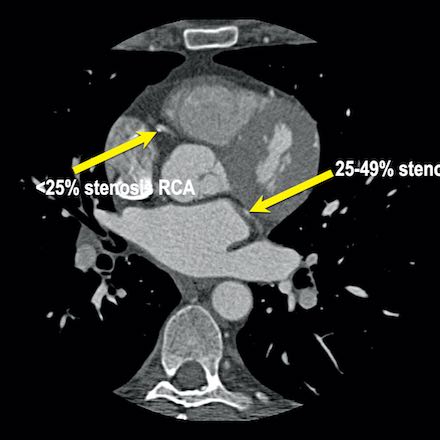

case 1 – CAD-RADS 2/P1

First, scroll through the scan.

Not all images are included. Some images without any abnormalities are skipped

from the series.

How would you describe the findings on the coronary CTA?

The findings are:

- Agatston score of

this patient was 14 (P1). Please, also note the calcification of the aortic valve. - Some partially

calcified and calcified plaques are present in the LAD with mild stenosis

(25-49%). - Calcified-plaque in

the LCX causing minimal stenosis (<25%). - Non-calcified

plaque in the distal RCA causing minimal stenosis (<25%). - This patient classifies

as CAD-RADS 2/P1, which means no further workup is needed.